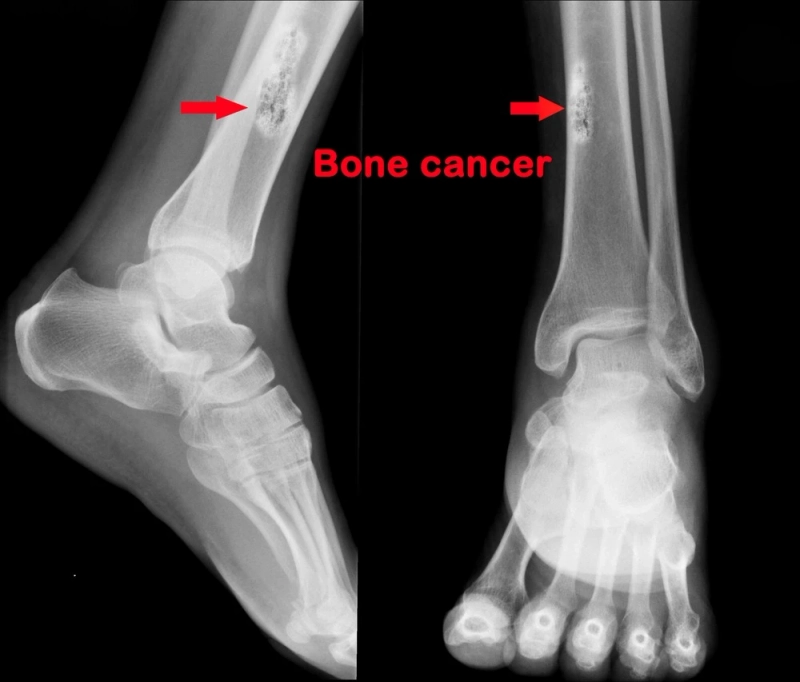

Diagnostic Analysis:

Accurate diagnosis involves imaging studies, such as X-rays and MRIs, along with biopsies to analyze the nature of the tumor. Precise diagnostic analysis guides treatment decisions and prognostic assessments.